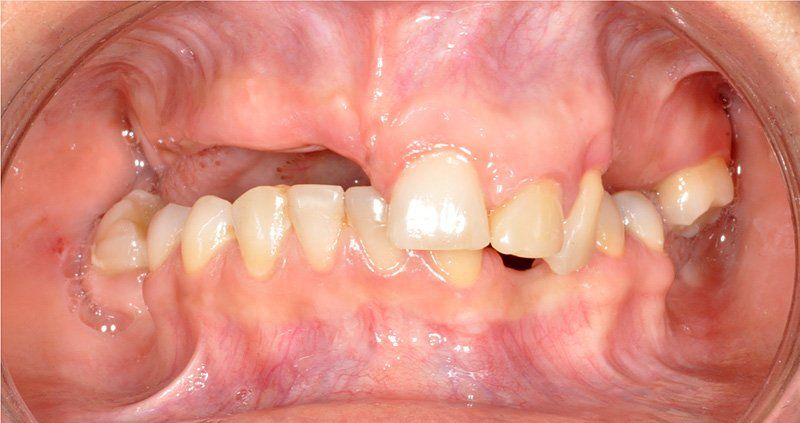

Los Implantes de Carga Inmediata son una solución práctica y definitiva para el desdentado total, es un tratamiento el cual una vez que se opera y se colocan los implantes, por un periodo entre 24 horas a 48 horas, se colocan los dientes en forma provisional, de esta forma el paciente queda con algo fijo mientras el implante se adhiere al hueso. Su principal ventaja radica en la reducción o eliminación del tiempo de espera entre la colocación del implante dental y la colocación de los dientes fijos.

Porque se hace en pabellones certificados por la Universidad de Chile. Son dependencias hechas única y exclusivamente para hacer intervención en sitios estériles. También se hace más cómodo y se pasa rápido el periodo de espera. Del momento en que se insertan los implantes debe transcurrir un período de tiempo de entre 4 a 6 meses si es en mandíbula o maxilar superiores respectivamente para que el tejido óseo cicatrice y logre integrarse a la superficie del implante